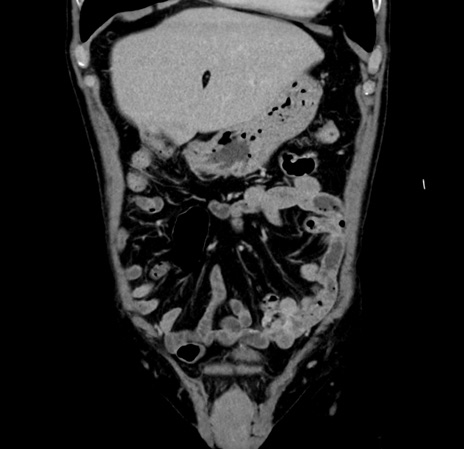

【腹部TIPS】症例70 CT(冠状断像)

【症例】60歳代 男性

とある所見でフォローされている。診断は?

CT

横断像